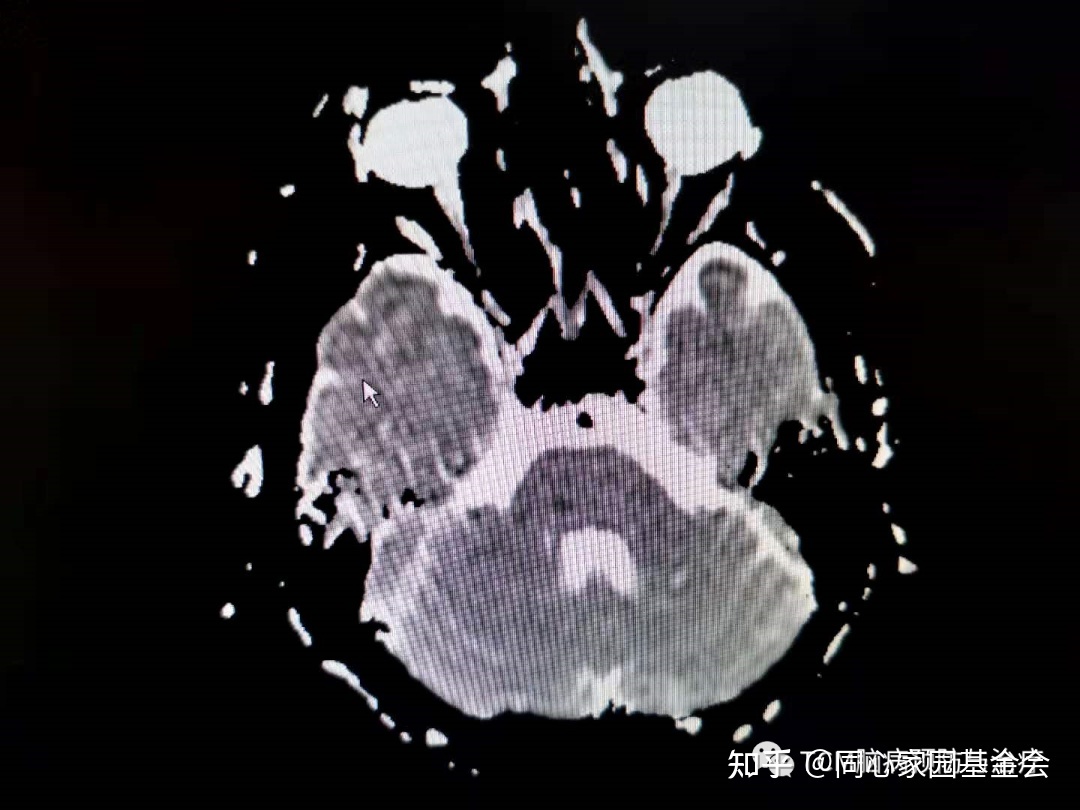

门诊查颅脑MRI如下:

诊断:急性脑梗死(桥脑),收入住院治疗,以急性脑梗死方案对症治疗。